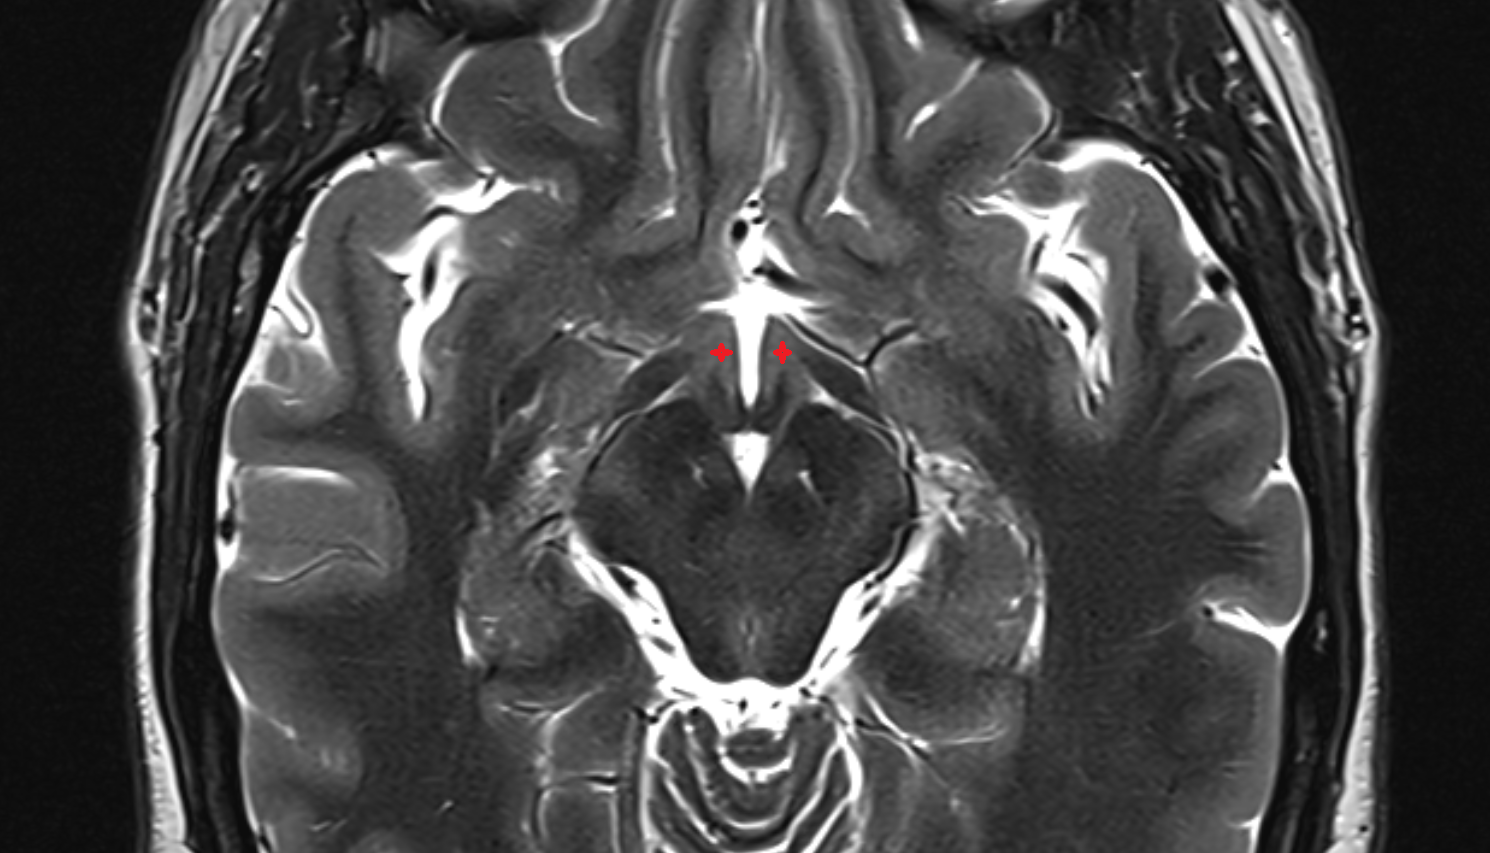

- Hippocampus